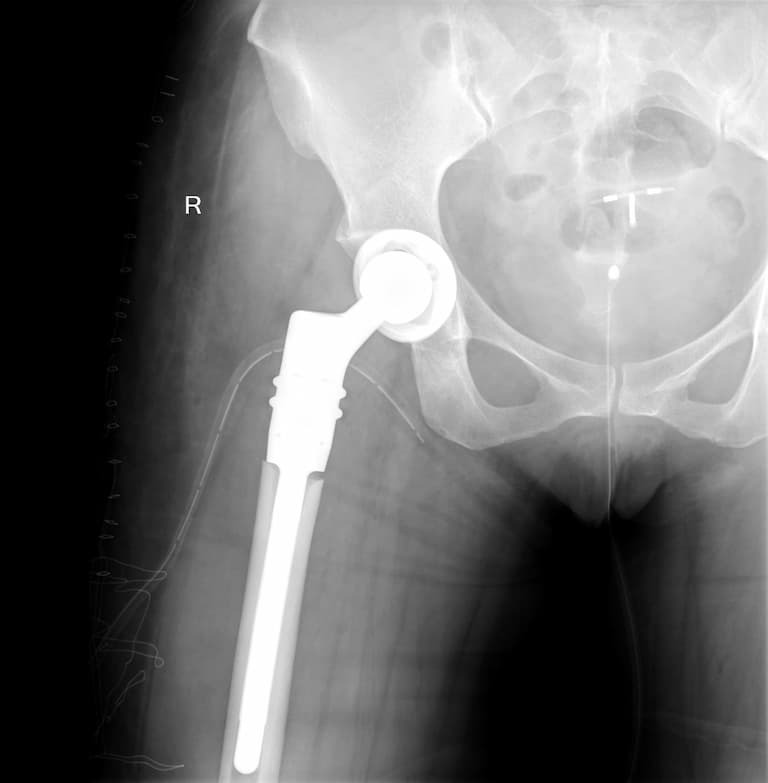

Мэс заслын өмнөх болон дараах рентген зураг

Түнхний үе солих мэс засал гэж юу вэ image4Түнхний үе солих мэс засал гэж юу вэ image5

Түнхний үе солих мэс засал гэж юу вэ image6Түнхний үе солих мэс засал гэж юу вэ image7